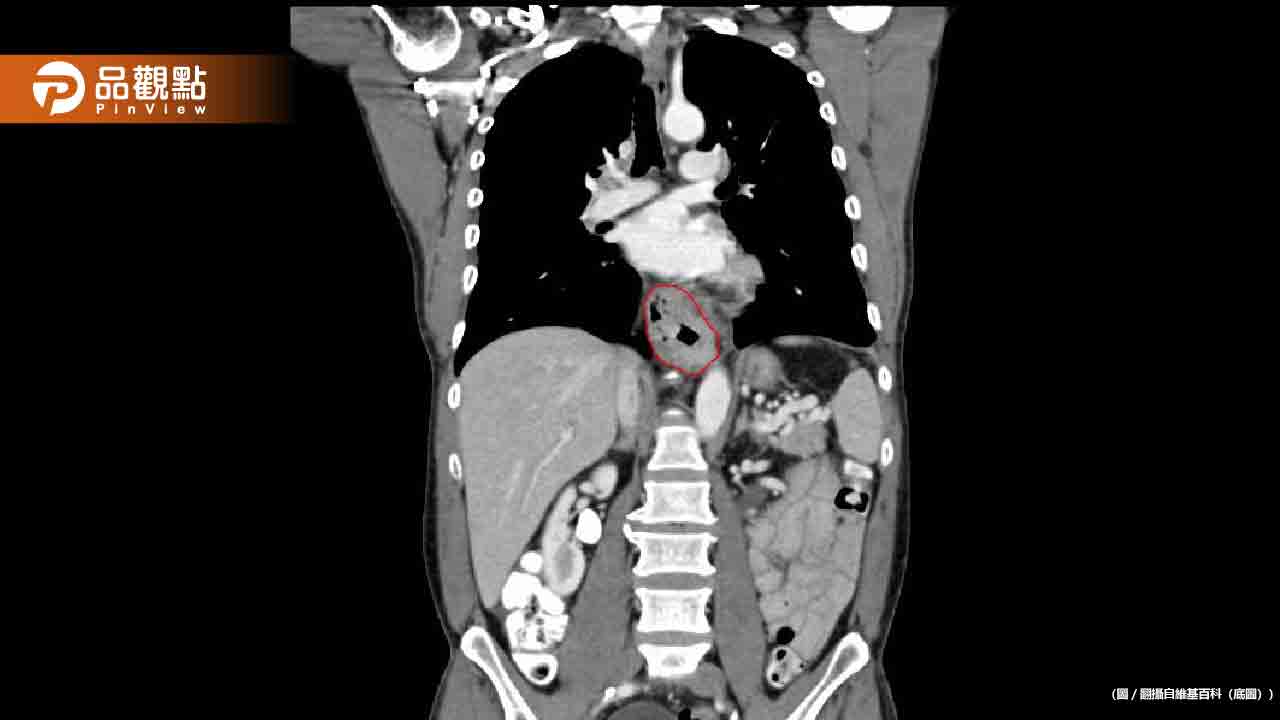

近日,一名60歲婦人因吞嚥困難、半年內體重狂掉8公斤就醫,經檢查後被診斷為食道癌末期,且已轉移至肺部和肝臟。醫師在詢問患者的生活習慣後,發現她長期存在高致癌風險的不良行為。